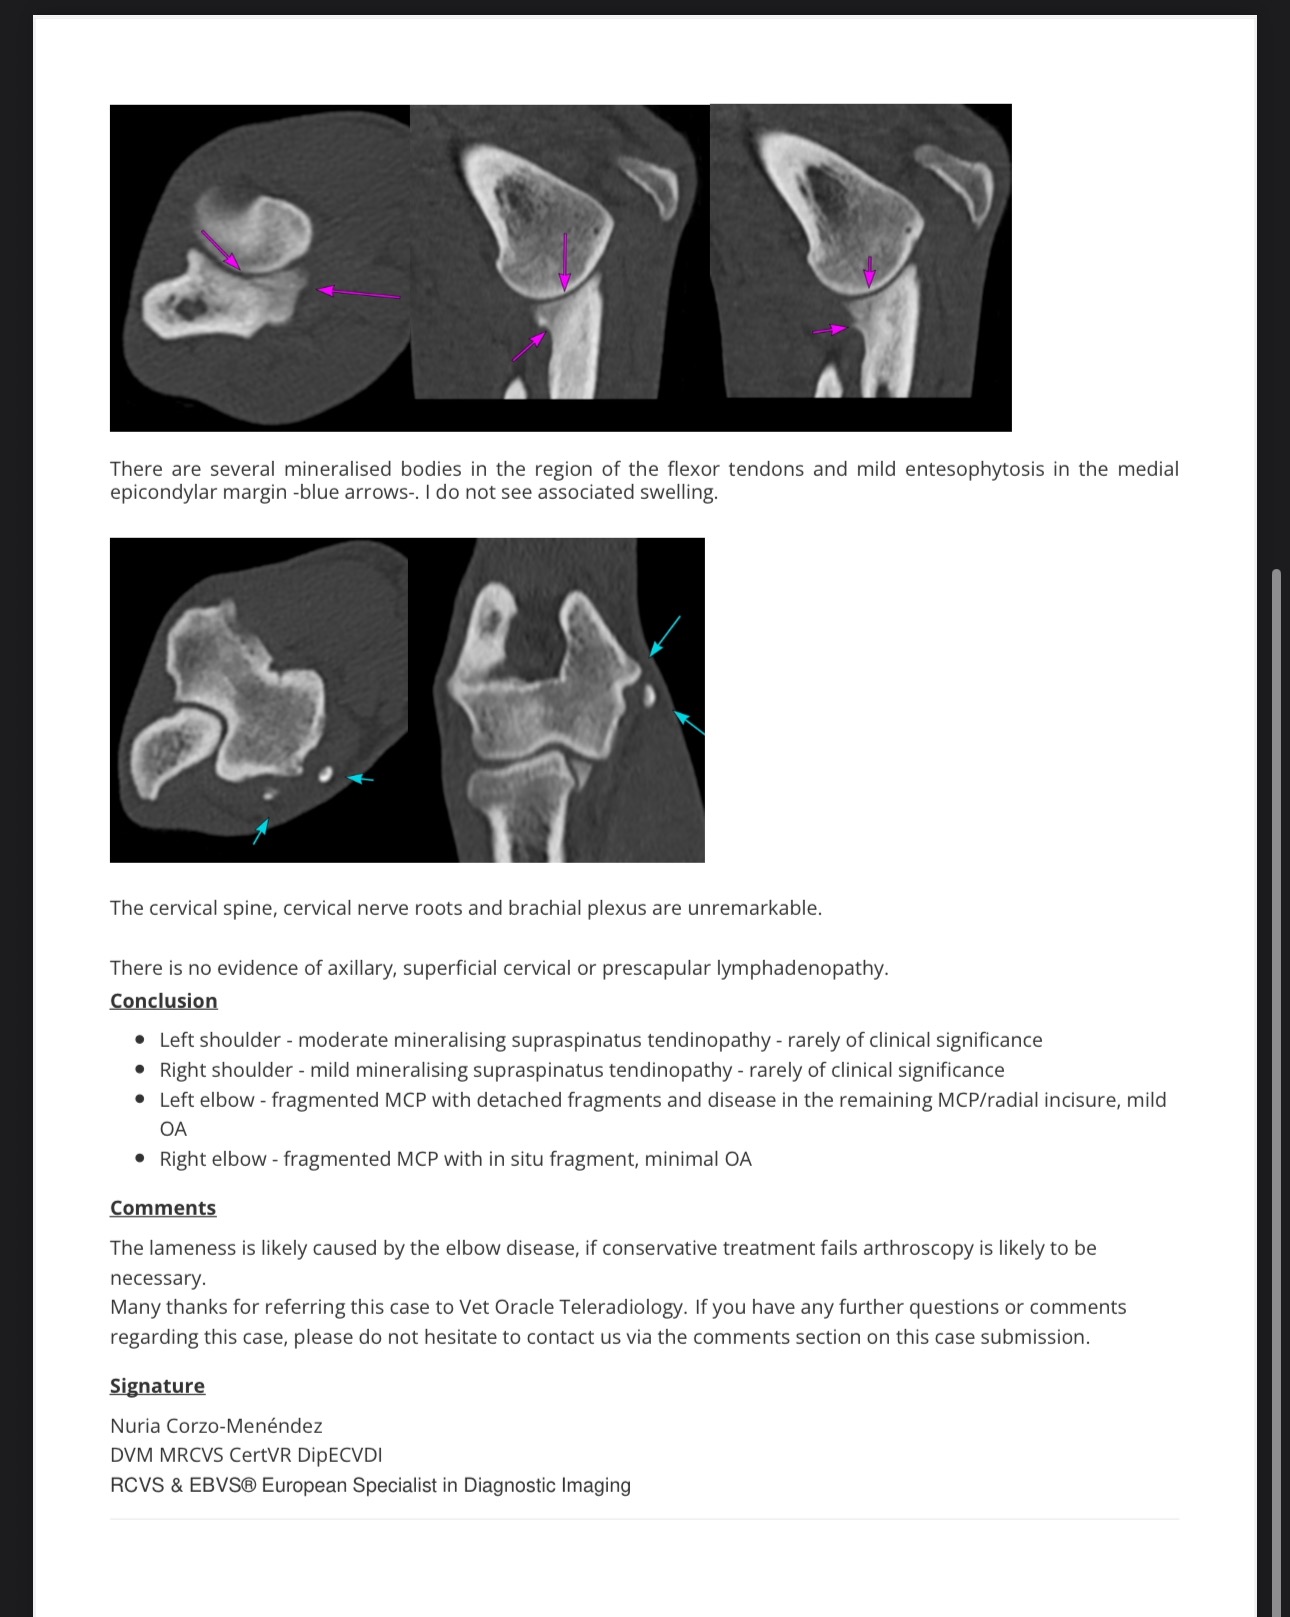

After a few difficult weeks, our beloved Labrador Romeo has been diagnosed with elbow coronoid disease and arthritis — a painful condition that affects the joints in his front legs and causes long-term pain, stiffness, and mobility issues.

Romeo has already undergone surgery to remove the damaged bone in his elbow. The total cost of his care so far is £6,125, which includes surgery, scans, medication, and follow-up treatment. We are now working to pay off this amount while also preparing for the ongoing care he’ll need, including physiotherapy, hydrotherapy, and regular medication.